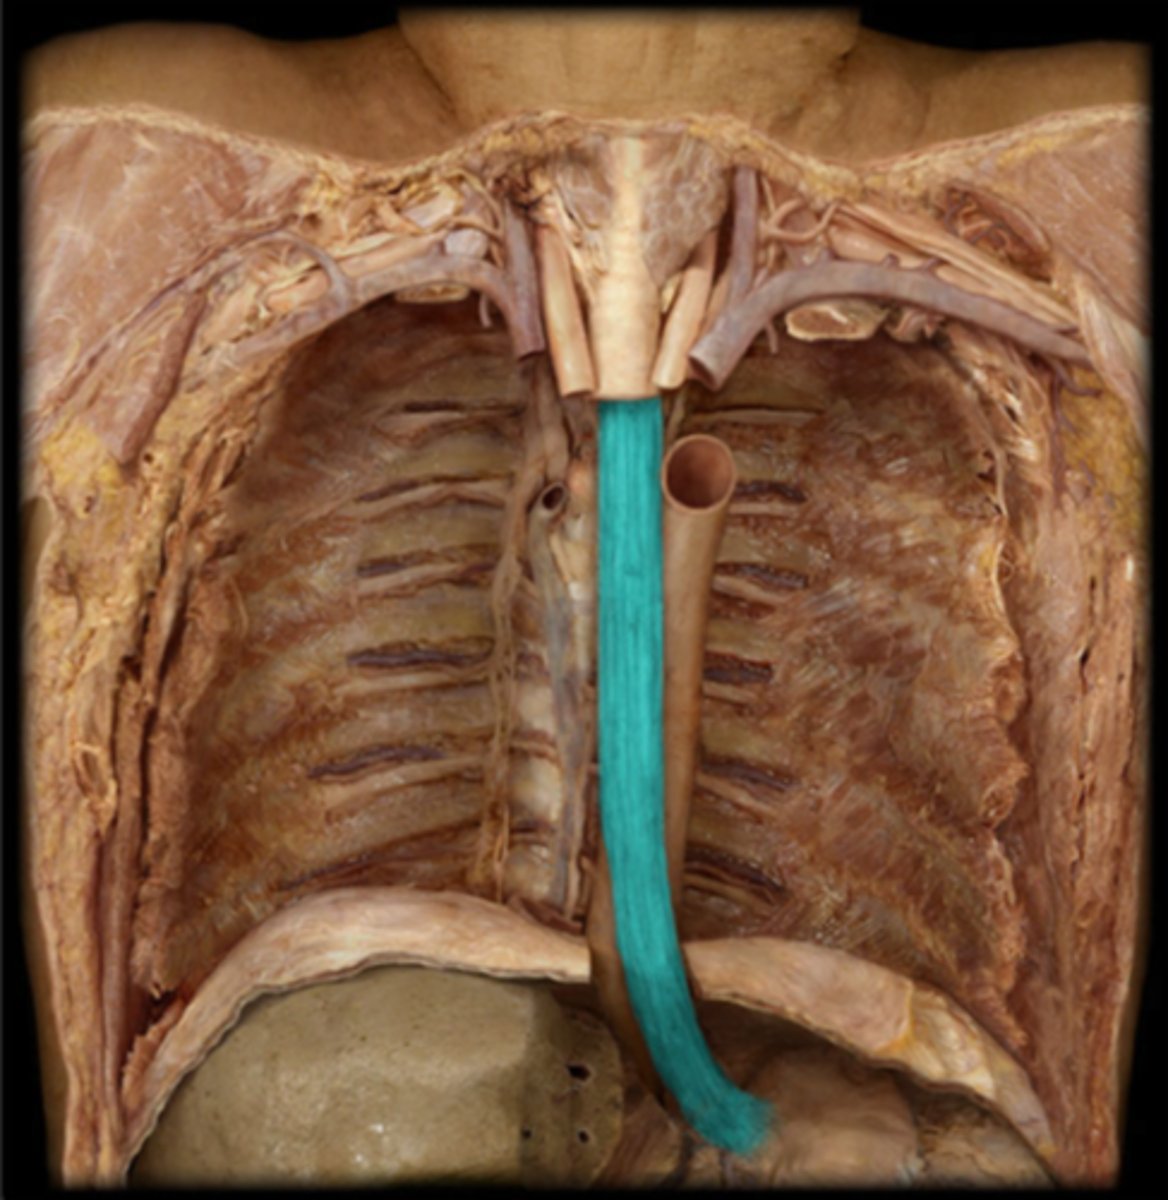

Esophagus

Trachea

Carina

Right Primary Bronchus

Left Primary Bronchus